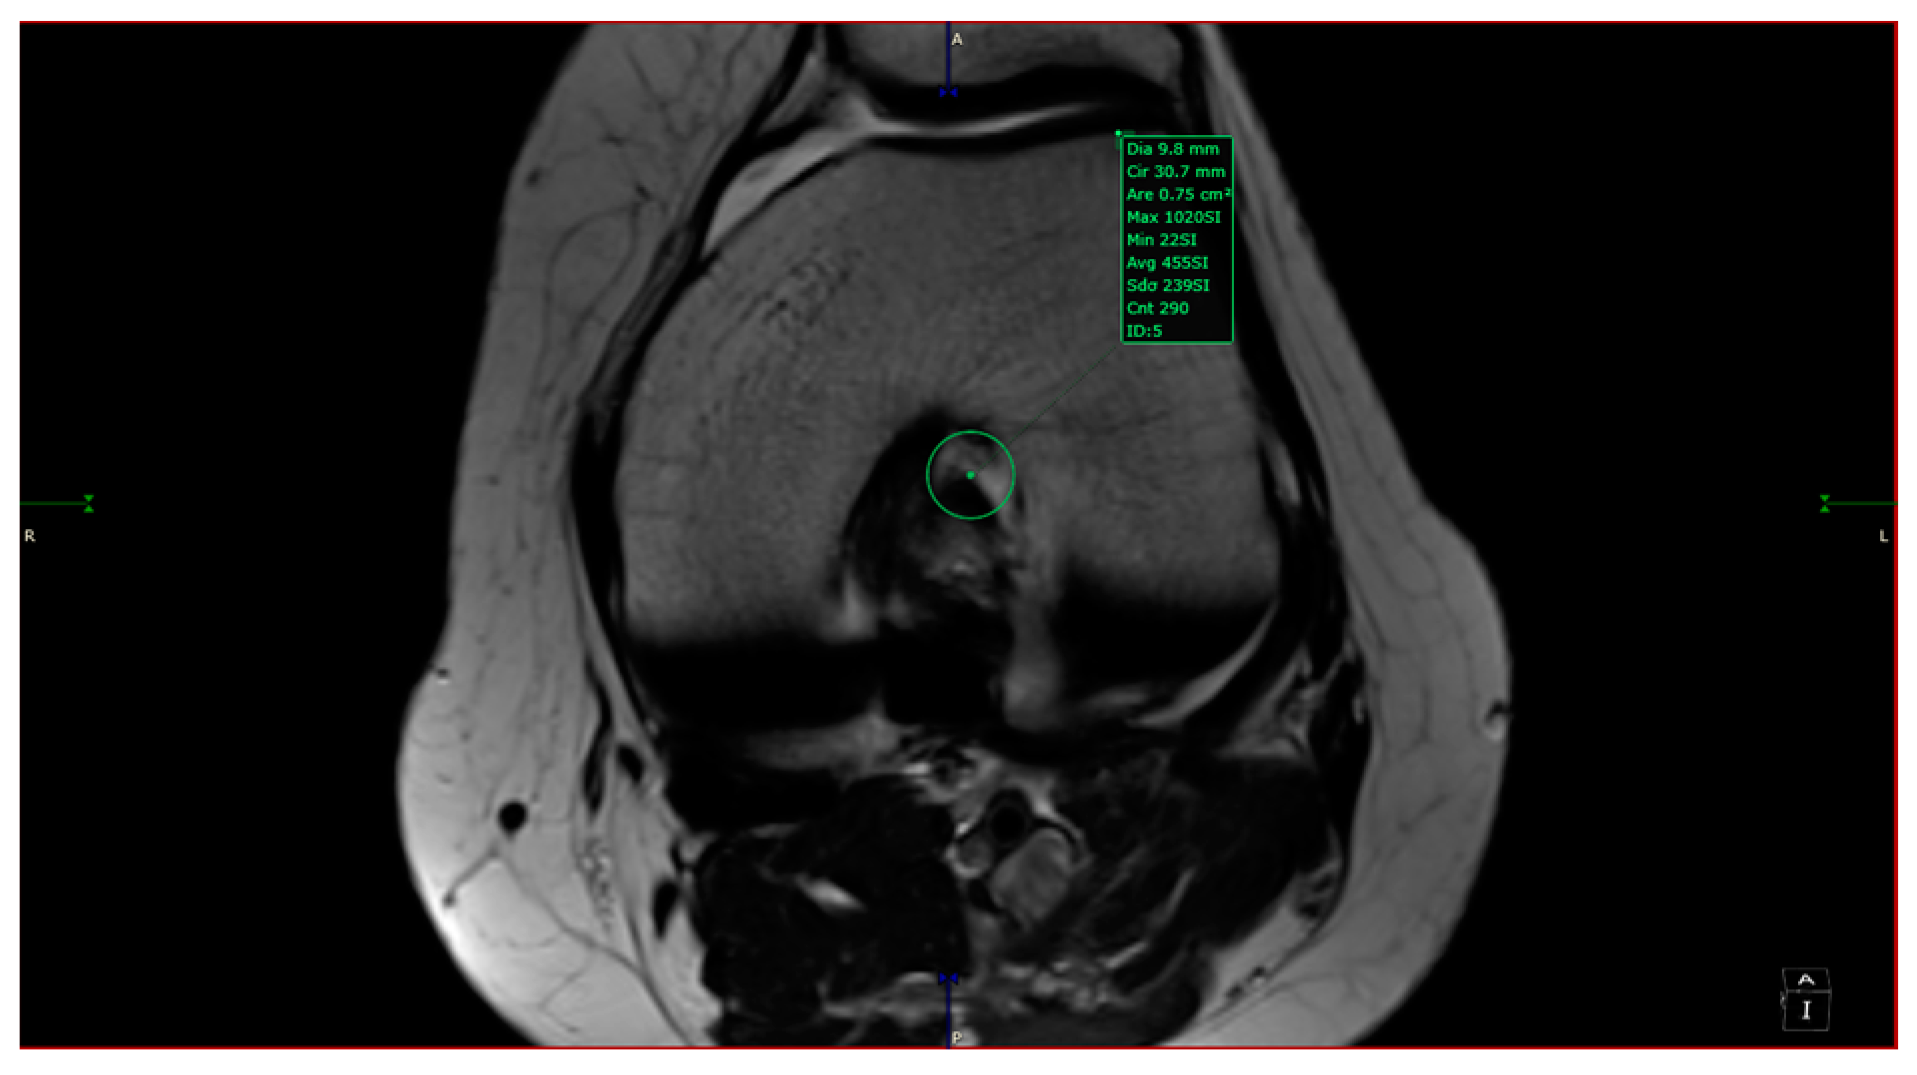

- aICN area: area of the circle defined by three cortical walls of the antero-superior notch (in the custom axial plane/CAP; Figure 3).

- aICN area and ACL area (both appear in Figure 6).